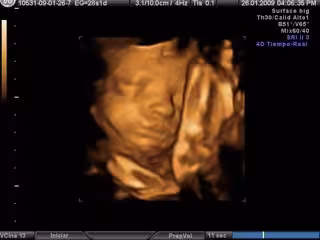

Ecografía en 3D- embarazo

Un equipo de investigadores de la Universidad Complutense de Madrid (UCM) ha descrito los cinco estadios de la formación de la glándula submandibular en embriones humanos, situándolos entre la quinta y la octava semana de desarrollo postconcepción.